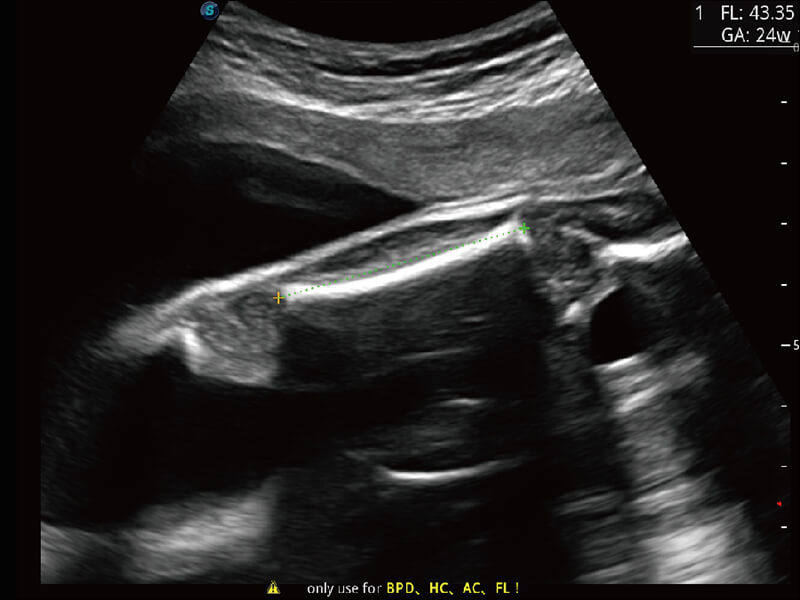

性能优异的硬件架构,极大提升超声系统的运行效率和数据处理能力。相比以往超声成像系统,Wis+平台为您带来极快的响应速度和成像帧频,提升检查流畅度。

超宽频带技术,为容积成像带来优质的二维图像基础,为您呈现丰富的结构细节,栩栩如生地展示宝宝的宫内形态以及各种组织的立体结构。